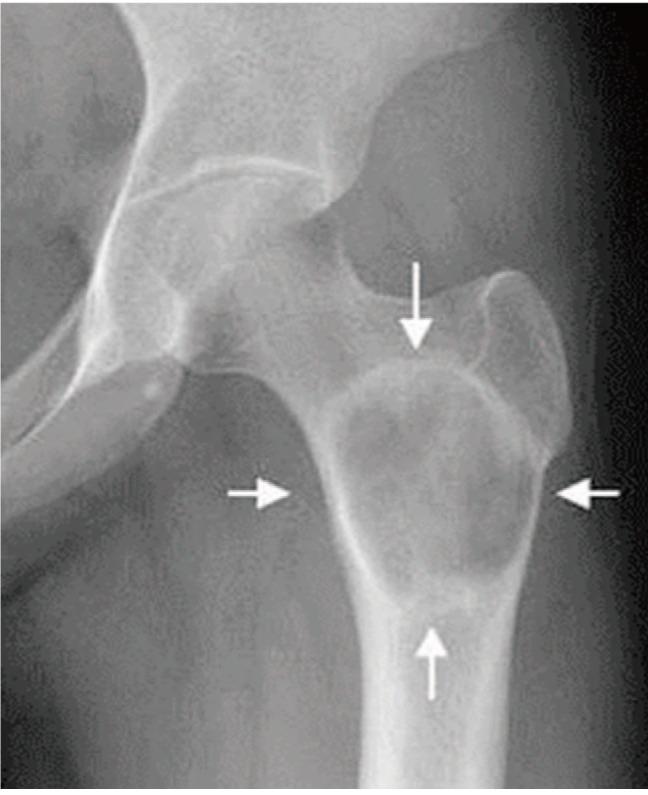

We report the case of a 25-year-old woman presenting with left hip pain. A lesion was found in the proximal femoral metaphysis. Benign bone tumor, such as intraosseous lipoma or liposclerosing myxofibrous tumor, was suspected based on simple radiographs and magnetic resonance images. Curettage of the lesion and bone grafting was performed. Histologic findings reflected primary intraosseous xanthoma of the proximal femur. Laboratory tests revealed the patient to be normolipidemic, while immunoelectrophoretic fractionation of lipoproteins revealed normal values for alpha, pre-beta, beta, and chylomicrons. At the one-year follow-up, there was no evidence of local recurrence. This is the first reported case of primary intraosseous xanthoma of the proximal femur in a normolipidemic patient.

我们报告了一例25岁女性因左髋部疼痛就诊的病例。在股骨近端干骺端发现一个病灶。基于普通X线片和磁共振成像,怀疑为良性骨肿瘤,如骨内脂肪瘤或脂肪硬化性黏液纤维瘤。对病灶进行了刮除和植骨。组织学检查结果显示为股骨近端原发性骨内黄瘤。实验室检查显示患者血脂正常,而脂蛋白免疫电泳分离显示α、前β、β和乳糜微粒值正常。在一年的随访中,没有局部复发的迹象。这是首例血脂正常患者的股骨近端原发性骨内黄瘤报告病例。